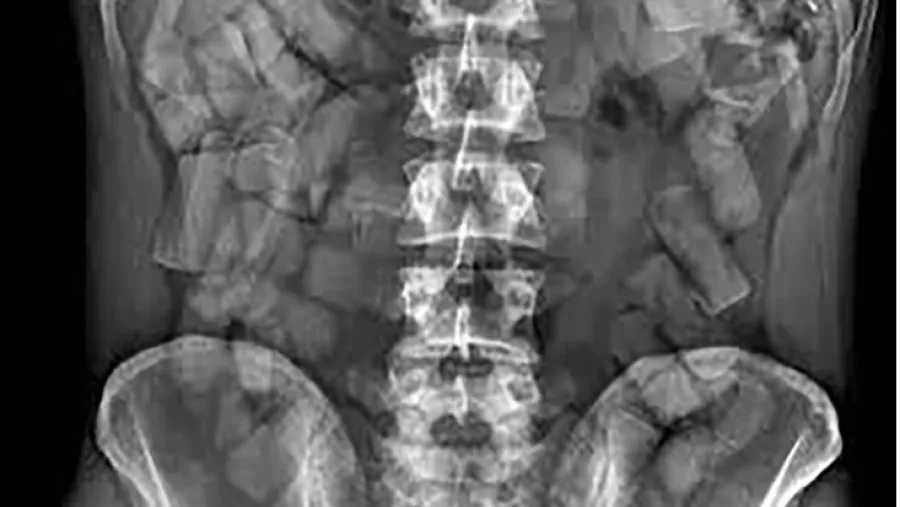

Por dentro: paquetes dentro del estómago de una mula detenida en Aeroparque.

Las detenciones comenzaron a repetirse en las terminales y en los barrios de la Patagonia en los últimos años, con bandas pesadas detrás de los kilos. El caso de Cristian Espinoza, excantante de Yerba Brava, detenido en abril de este año en Aeroparque con casi un kilo distribuido entre su estómago y sus genitales se enmarca, dicen fuentes en Tribunales, en esta lógica.